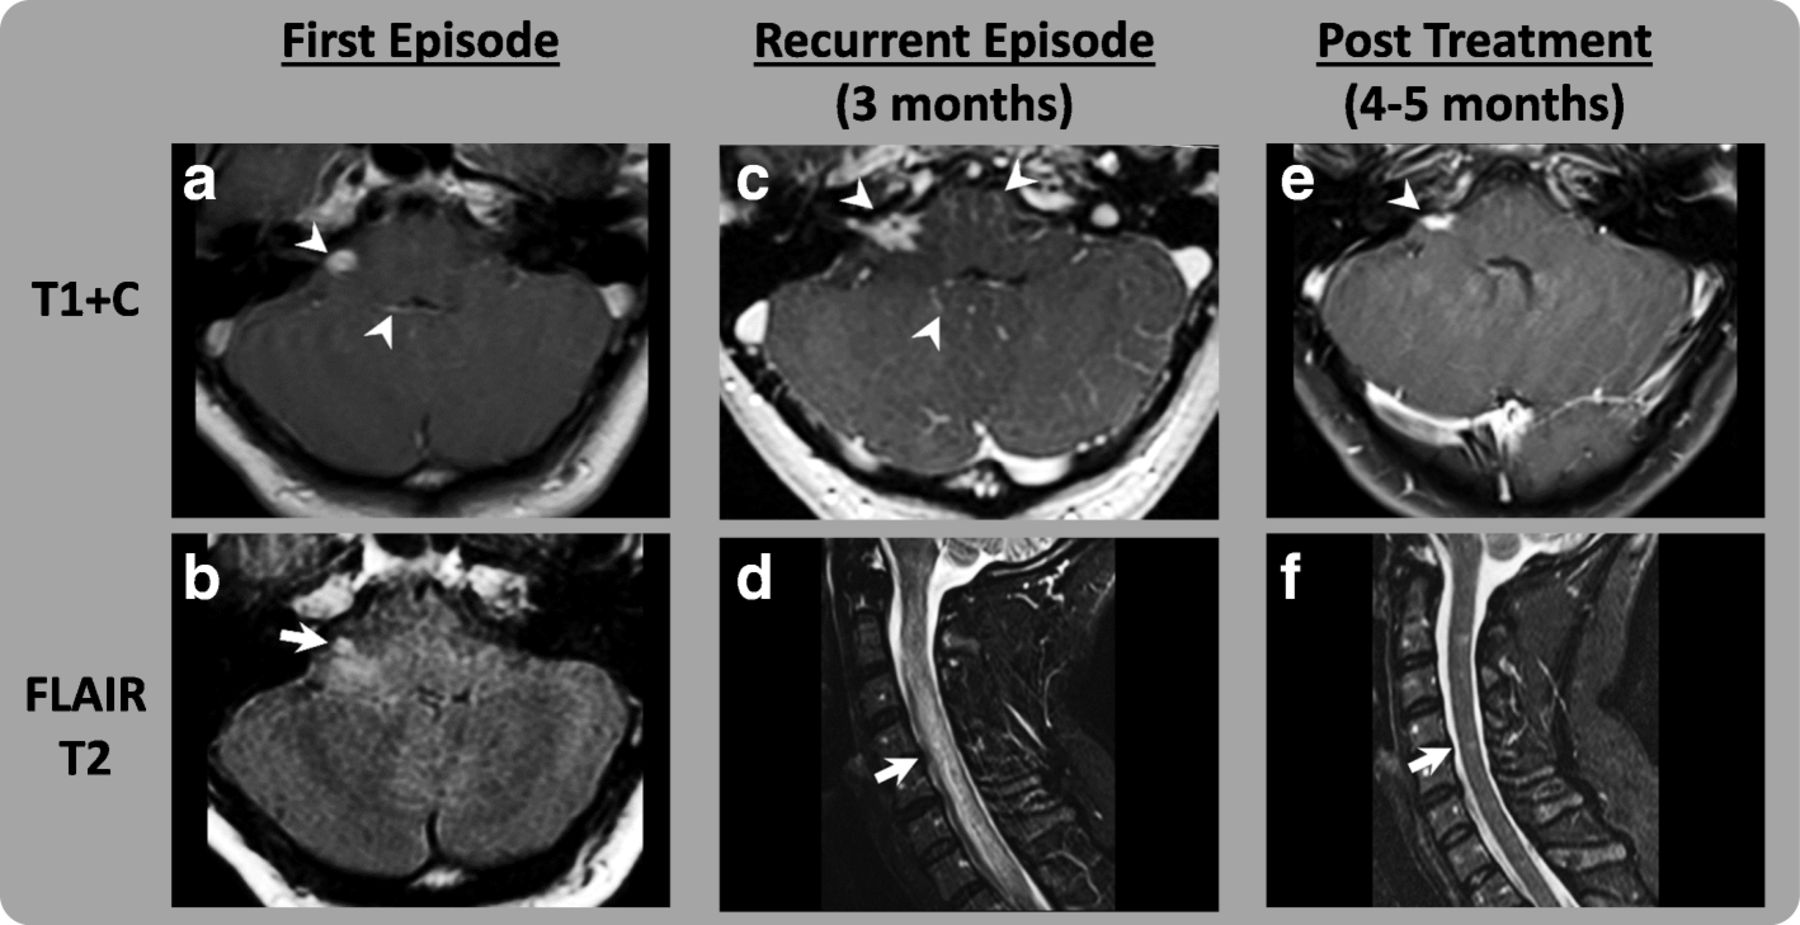

Back Pain And Radiculopathy From Non Steroidal Anti Inflammatory

Contribution Of Arterial Spin Labelling Mri In A Case With Immune

A Severe Case Of Neuro Sjogren S Syndrome Induced By Pembrolizumab

Neurologic Immune Related Adverse Events Associated With Adjuvant